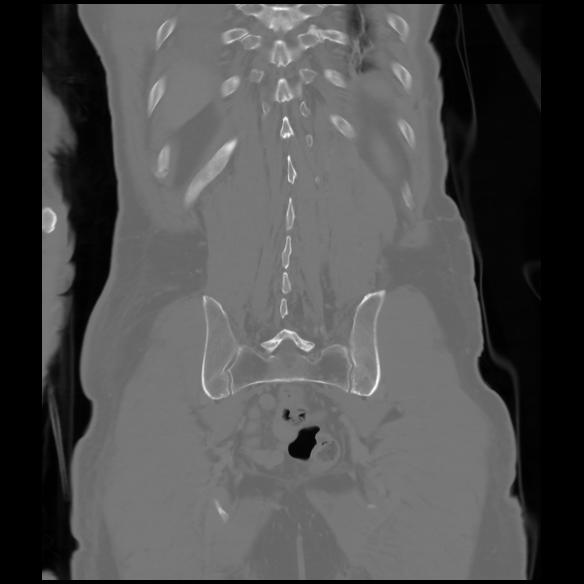

6 CUERPO,CE,Coronal,3.000,CUERPO,Coronal,